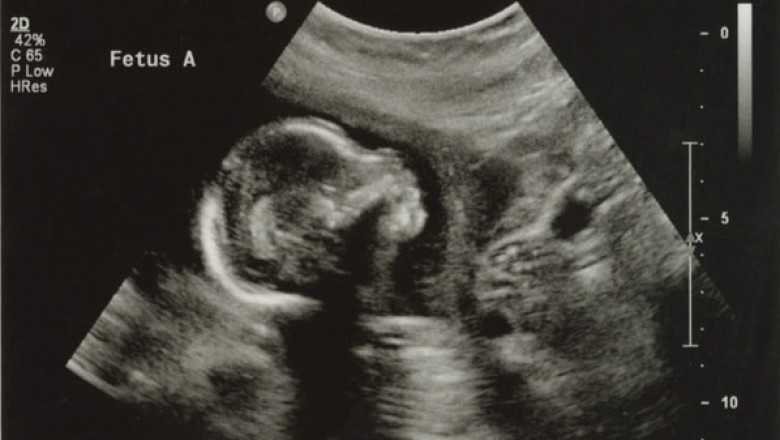

Dr. Anmol’s Ultrasound Clinic is the ideal clinic to go for level 2 ultrasound in pregnancy. We have the best ultrasound services to offer nearby Gurgaon.

Dr. Anmol’s Ultrasound Clinic is the ideal clinic to go for level 2ultrasound in pregnancy. We have the best ultrasound services to offernearby Gurgaon. Our clinic maintains a proper hygiene. We have thewell-qualified and friendly staff that is capable of understanding your needsand addressing your doubts.